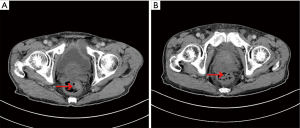

A recheck of the previous CT images from November 2017 showed a small, high-density shadow inside the rectal wall (Figure 5A) that was not observed in the images from September 2017 (Figure 5B). Because of the patient’s previous history of rectal polypectomy, the shadow was neglected by both the radiologist and the oncologist.